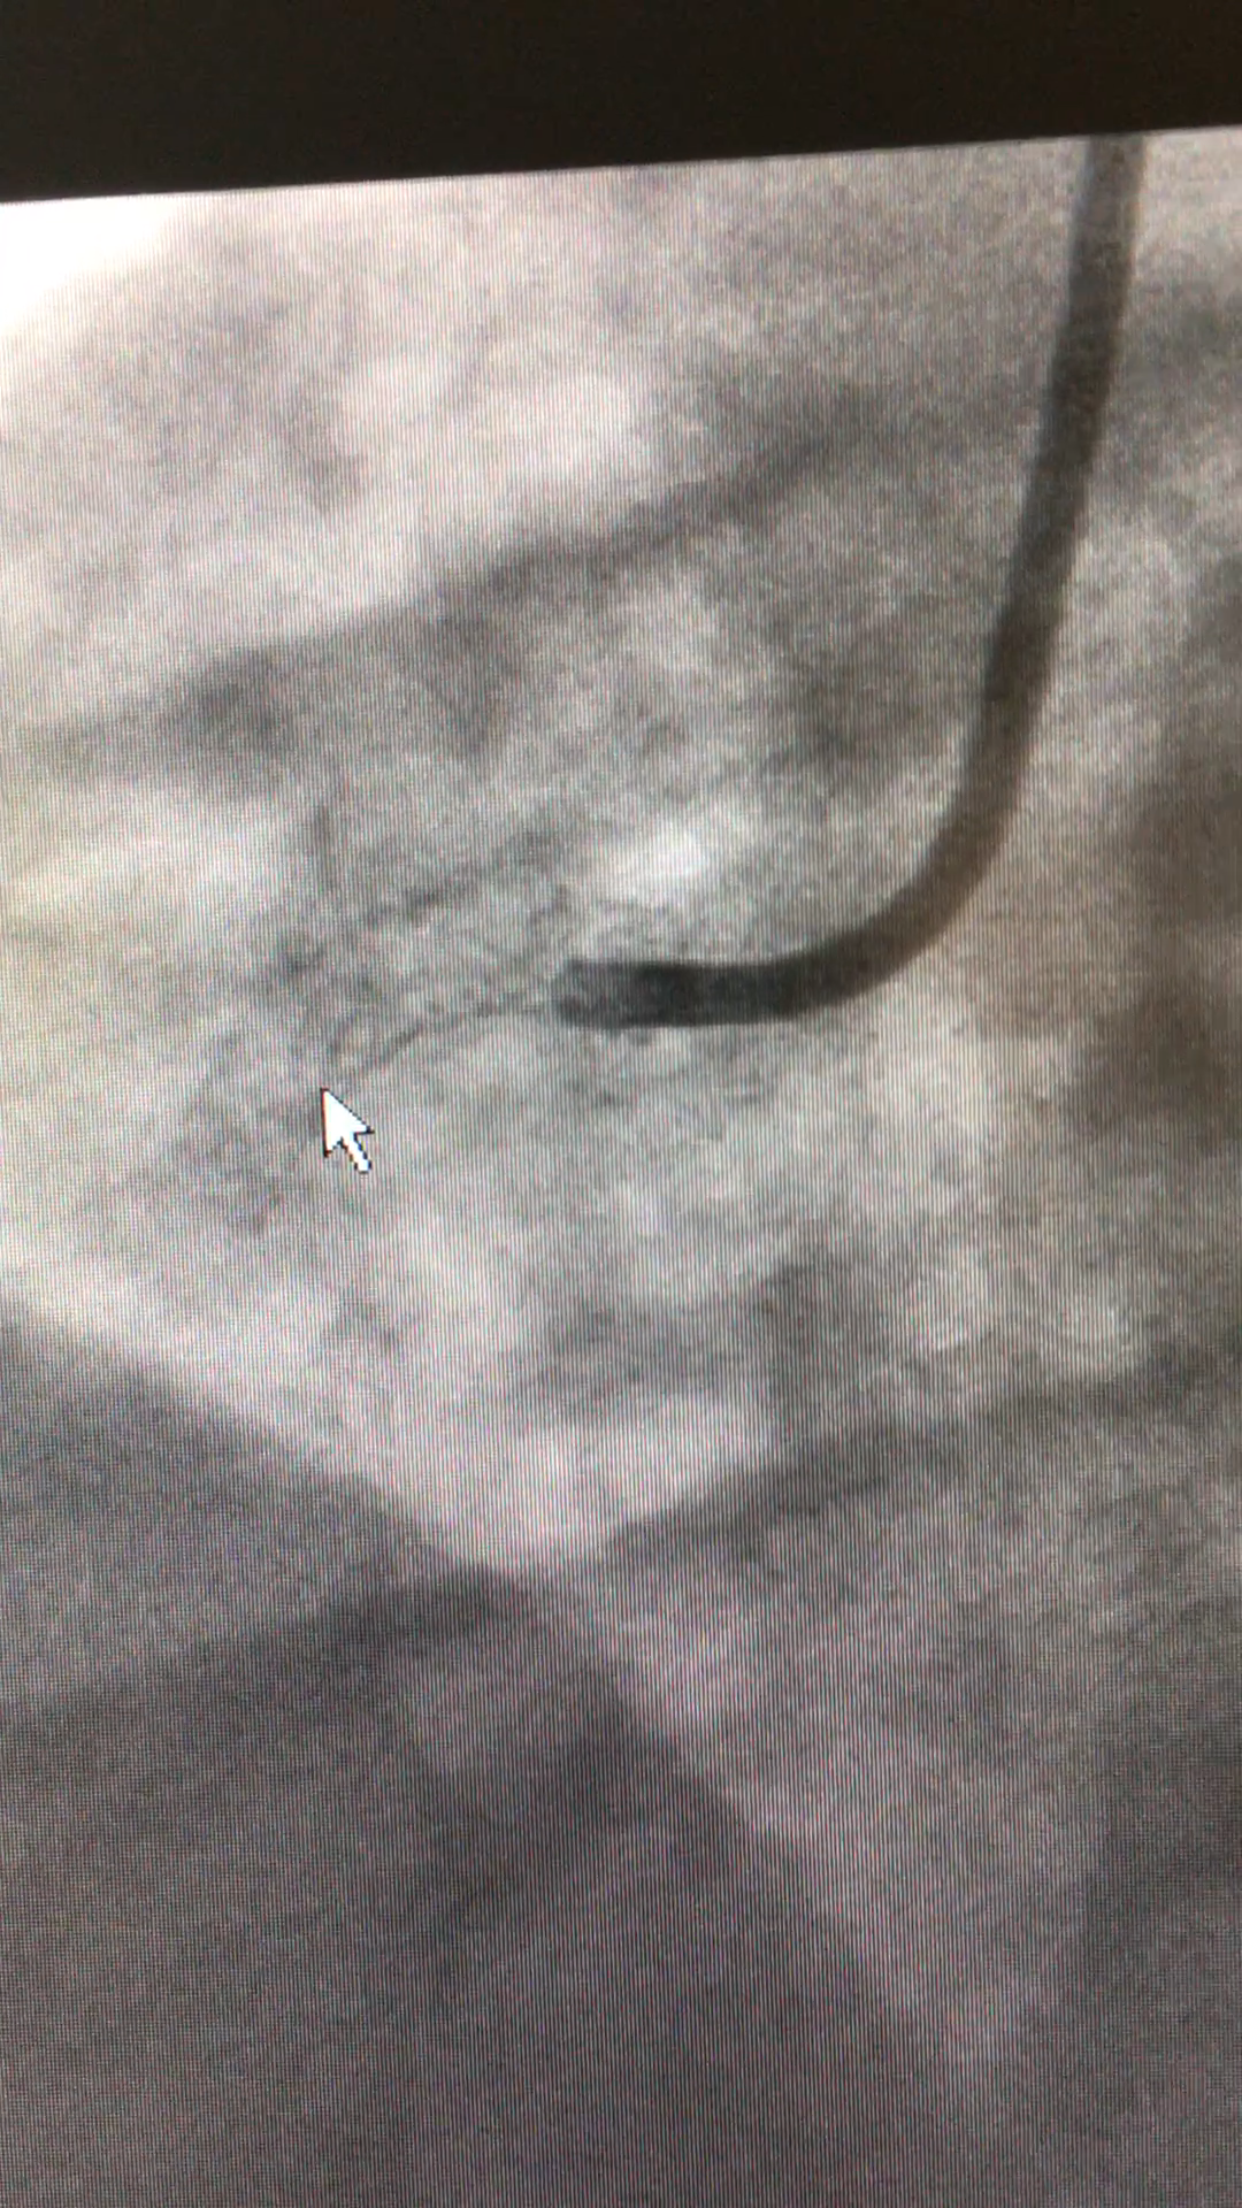

Below is a picture of my angiogram when they fixed my right coronary artery with the placement of stents.. this is why February is so important. February brought about the research and medical developments to open my artery and save my life!!

The white arrow points to the stent placed in my artery. This will allow my artery to stay open and bring blood to my heart.